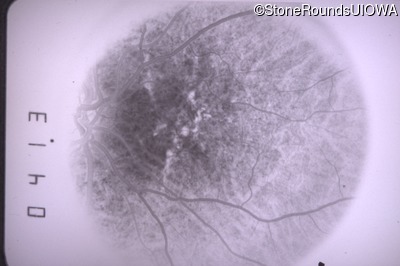

Fluorescein Angiography - Right - 20/20 sc

Exemplar

Fluorescein Angiography - Left - 20/15 -1 sc